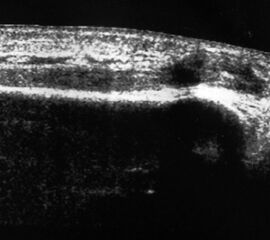

Referenzstruktur: Direkt unter der Haut und der dünnen Subkutis liegt echogen und straff parallel die Achillessehne mit ihrem echogenen Peritendineum (Abb. 53), Tuber calcanei.

Befunde: Da die Sehne zumeist nicht glatt, sondern bündelförmig reißt, stellen sich auch in der Sonographie anders als bei den Peroneal- und Flexorensehnen keine spargelspitzenähnlichen Rissenden dar. Echogene Rissränder, umgeben von echoarmem Hämatom sind beweisend für eine Ruptur. Risse der Achillessehne können auch nur einen Teil des Sehnenquerschnitts betreffen. Daher ist die Untersuchung verschiedener TS bedeutsam (Abb. 54 bis 56). Unter Kontrolle am Monitor kann die Diagnose in maximaler Dorsalextension klarer gestellt werden (Abb. 57).